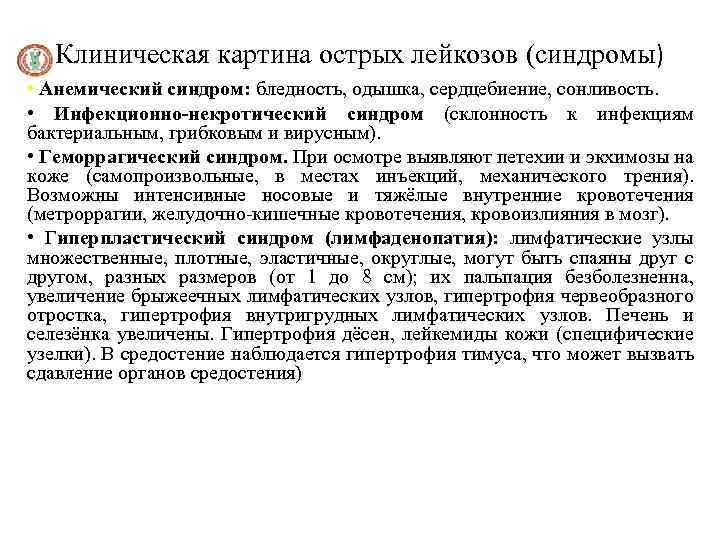

Клиническая картина острых лейкозов (синдромы) • Анемический синдром: бледность, одышка, сердцебиение, сонливость. • Инфекционно-некротический синдром (склонность к инфекциям бактериальным, грибковым и вирусным). • Геморрагический синдром. При осмотре выявляют петехии и экхимозы на коже (самопроизвольные, в местах инъекций, механического трения). Возможны интенсивные носовые и тяжёлые внутренние кровотечения (метроррагии, желудочно-кишечные кровотечения, кровоизлияния в мозг). • Гиперпластический синдром (лимфаденопатия): лимфатические узлы множественные, плотные, эластичные, округлые, могут быть спаяны друг с другом, разных размеров (от 1 до 8 см); их пальпация безболезненна, увеличение брыжеечных лимфатических узлов, гипертрофия червеобразного отростка, гипертрофия внутригрудных лимфатических узлов. Печень и селезёнка увеличены. Гипертрофия дёсен, лейкемиды кожи (специфические узелки). В средостение наблюдается гипертрофия тимуса, что может вызвать сдавление органов средостения)

Клиническая картина острых лейкозов Признаки специфического поражения: • Интоксикация: лихорадка, снижение массы тела, снижение аппетита, слабость, усиленная потливость. • Болезненность костей (особенно трубчатых, позвоночника), артралгии. • ДВС-синдром. • Нейролейкемия. (поражение центральной нервной системы) возникает особенно часто при остром лимфобластном лейкозе и значительно ухудшает прогноз. Возникновение нейролейкемии обусловлено метастазированием лейкозных клеток в оболочки головного и спинного мозга или в вещество мозга (интратумор, прогностически более тяжёлый тип опухолевого роста). В неврологическом статусе возможны проявления различной тяжести - от лёгкой общемозговой симптоматики (головная боль) до очаговых поражений (нарушение сознания, нарушение зрения, дискоординация движений, дисфазия)